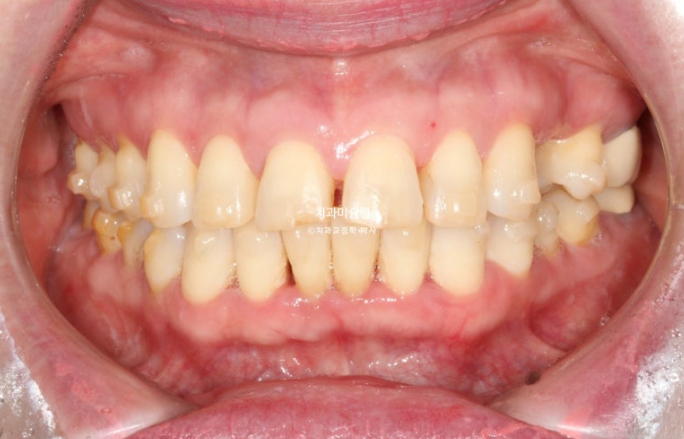

이제 전후 비교해보겠습니다.

24.07~26.01

앞니 각도의 개선이 눈에 띕니다.

아래 앞니는 치간삭제와 함입으로 위 앞니 사이사이 벌어진 공간을 이용하여 뻗친 각도와 골출을 개선하였으며

위 아래 앞니 각각 1.5-2mm 가량 뒤로 들어갔습니다.